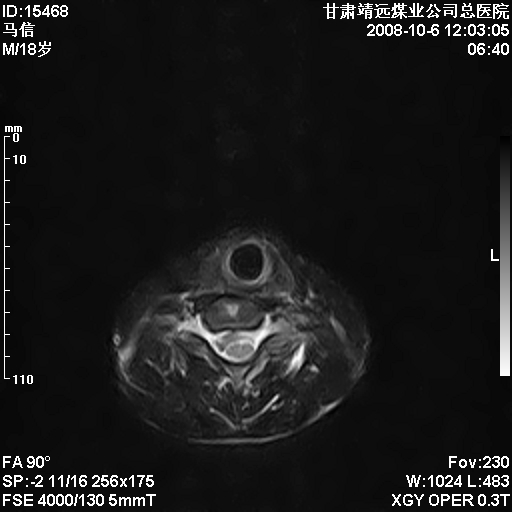

标题: MRI1827:颈椎内异常信号,是不是占位。

患者18岁,学生,在玩耍中受伤来检查,患者喜欢打篮球。颈椎内异常信号影,我们考虑占位,但是不像占位,又考虑硬膜囊的增厚,大家关建看颈椎椎管内的那个异常占位信号

脑脊液流动伪影?

后纵韧带增厚,颈2/3、3/4、4/5、5/6椎间盘变性、突出;椎体有旋转,提示椎小关节有问题;腰椎间盘变性,许莫氏结节。

是正常的脑脊液波动伪影

脑脊液流动伪影

你说的占位是伪影。在我们医院1.5t和3.0t的mr上是经常看见的。